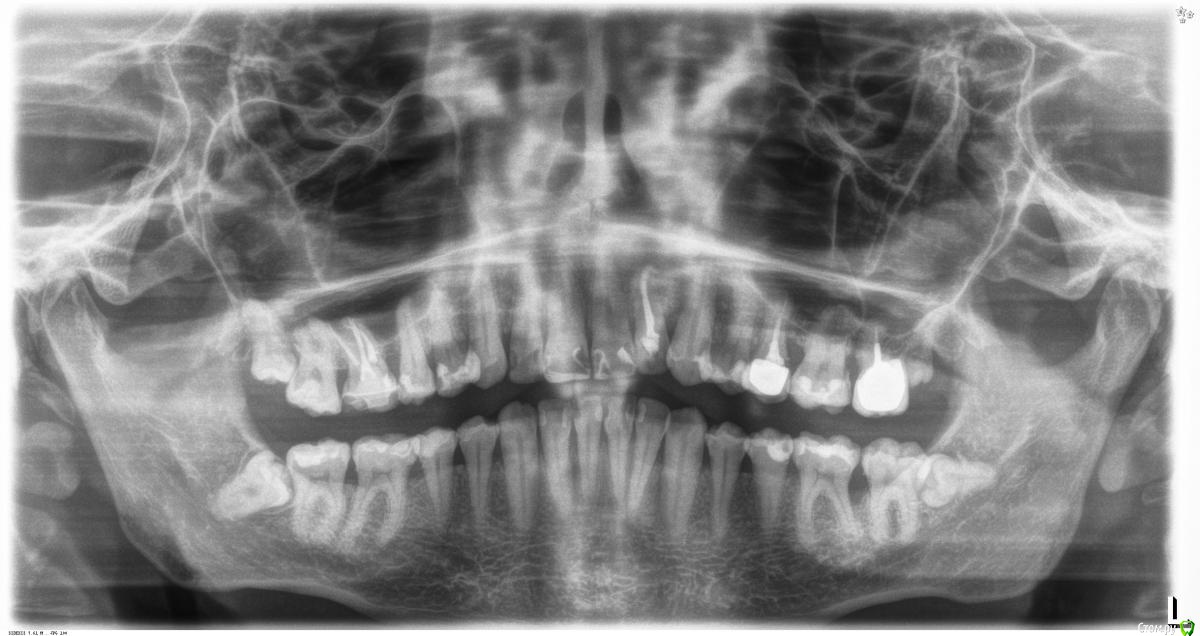

St. Опубликовано 19 февраля, 2018 Поделиться Опубликовано 19 февраля, 2018 Пациент 32лет, жалобы на боль в обл. 36-37 которую почувствовал вчера, ассиметрия лица. До этого не беспокоил никак, ни на температурные раздражители, ни на сладкое, ни на накусывание. В истории семейная предрасположенность к парадонтиту, соматически здоров.Пломбы на 36 37 нормальные, контакт есть, нависающих краев нет.Витальность не проверяли сегодня Пока хирург дал отток через карман и назначил антибиотики.Как вести дальше, какие шансы спасти 36? Ссылка на комментарий

St. Опубликовано 20 февраля, 2018 Автор Поделиться Опубликовано 20 февраля, 2018 Как прийдёт проверю.Кстати, подвижность 36 1 степени, 37 неподвижен.Вот панорама годичной давности. Карман был, но явно не такой. Ссылка на комментарий

vse32 Опубликовано 20 февраля, 2018 Поделиться Опубликовано 20 февраля, 2018 Вот панорама годичной давности. Карман был, но явно не такой. Не. Тогда без всяких эндо. Просто удалять. Ссылка на комментарий